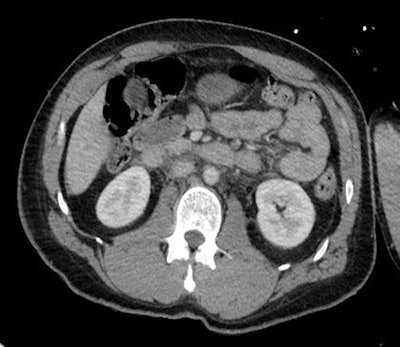

Inferior vena cava (IVC) flattening is likely to represent overall circulatory failure in hypotensive patients, they continued. It is defined as an anterior-posterior diameter of less than 9 mm at three levels: within the intrahepatic portion of the IVC, at the level of the renal arteries, and 2 cm below the level of the renal arteries.

The so-called IVC halo sign refers to accumulation of extracellular fluid (HU < 20) around a collapsed IVC.

"It is present in up to 80% of hypovolemic patients, and occurs due to loss of precapillary arteriolar sphincter tone with accumulation of fluid surrounding the IVC," Power and colleagues wrote. "While periportal edema is commonly seen in biliary cirrhosis or hepatitis, it can rarely be encountered in patients following vigorous intravenous fluid resuscitation."

As for the small caliber aorta, narrowing of the anteroposterior (AP) diameter of the abdominal aorta can occur in response to hypovolemia. This results from an intense sympathetic response to decreased circulating fluid volume, and is defined as an AP aortic measurement of less than 13 mm at 2 cm above, at, and 2 cm below the origin of the renal artery, they pointed out.

In hypovolemia cases, there is acute activation of the renin-angiotensin system. This causes a dramatic increase in resistance of the efferent renal arteriole, and results in an intense, prolonged cortical renal enhancement.